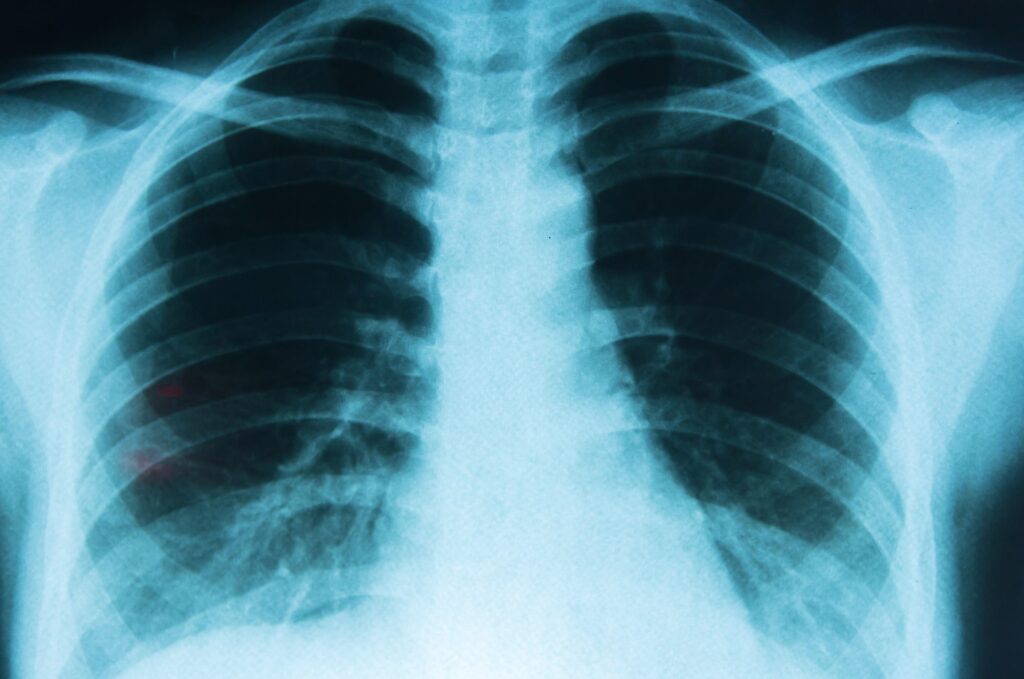

Síntomas iniciales del cáncer de pulmón

La falta de información y la confusión sobre los síntomas más iniciales de la enfermedad siguen retrasando el diagnóstico temprano. Según los datos que aporta el informe Emociones y experiencias de las personas con cáncer de pulmón, elaborado por la AEACaP y la Fundación Más que Ideas, 3 de cada 4 pacientes diagnosticados de cáncer de pulmón no saben reconocer las primeras señales de alarma de esta patología.

Los síntomas más habituales antes del diagnóstico son los siguientes (ordenados según su frecuencia):

- Tos persistente (25,5%).

- Cansancio o debilidad (19,8%).

- Dolor torácico (19,8%).

- Dificultad para respirar (13,2%).

- Pérdida de peso sin explicación (10,8%).

Al tratarse de manifestaciones que se pueden asociar a otras enfermedades de carácter leve, 1 de cada 3 pacientes tarda más de un mes en acudir al médico desde la aparición de los primeros indicios, lo que retrasa el inicio del tratamiento y reduce las posibilidades de éxito. “Si detectamos algunas de estas señales o varias de ellas de forma recurrente o persistente, sí deberíamos acudir al médico a hacernos un chequeo. Lo más probable es que no sea nada grave, pero si lo es, al menos intentaremos detectarlo cuanto antes”, resalta Gaspar.